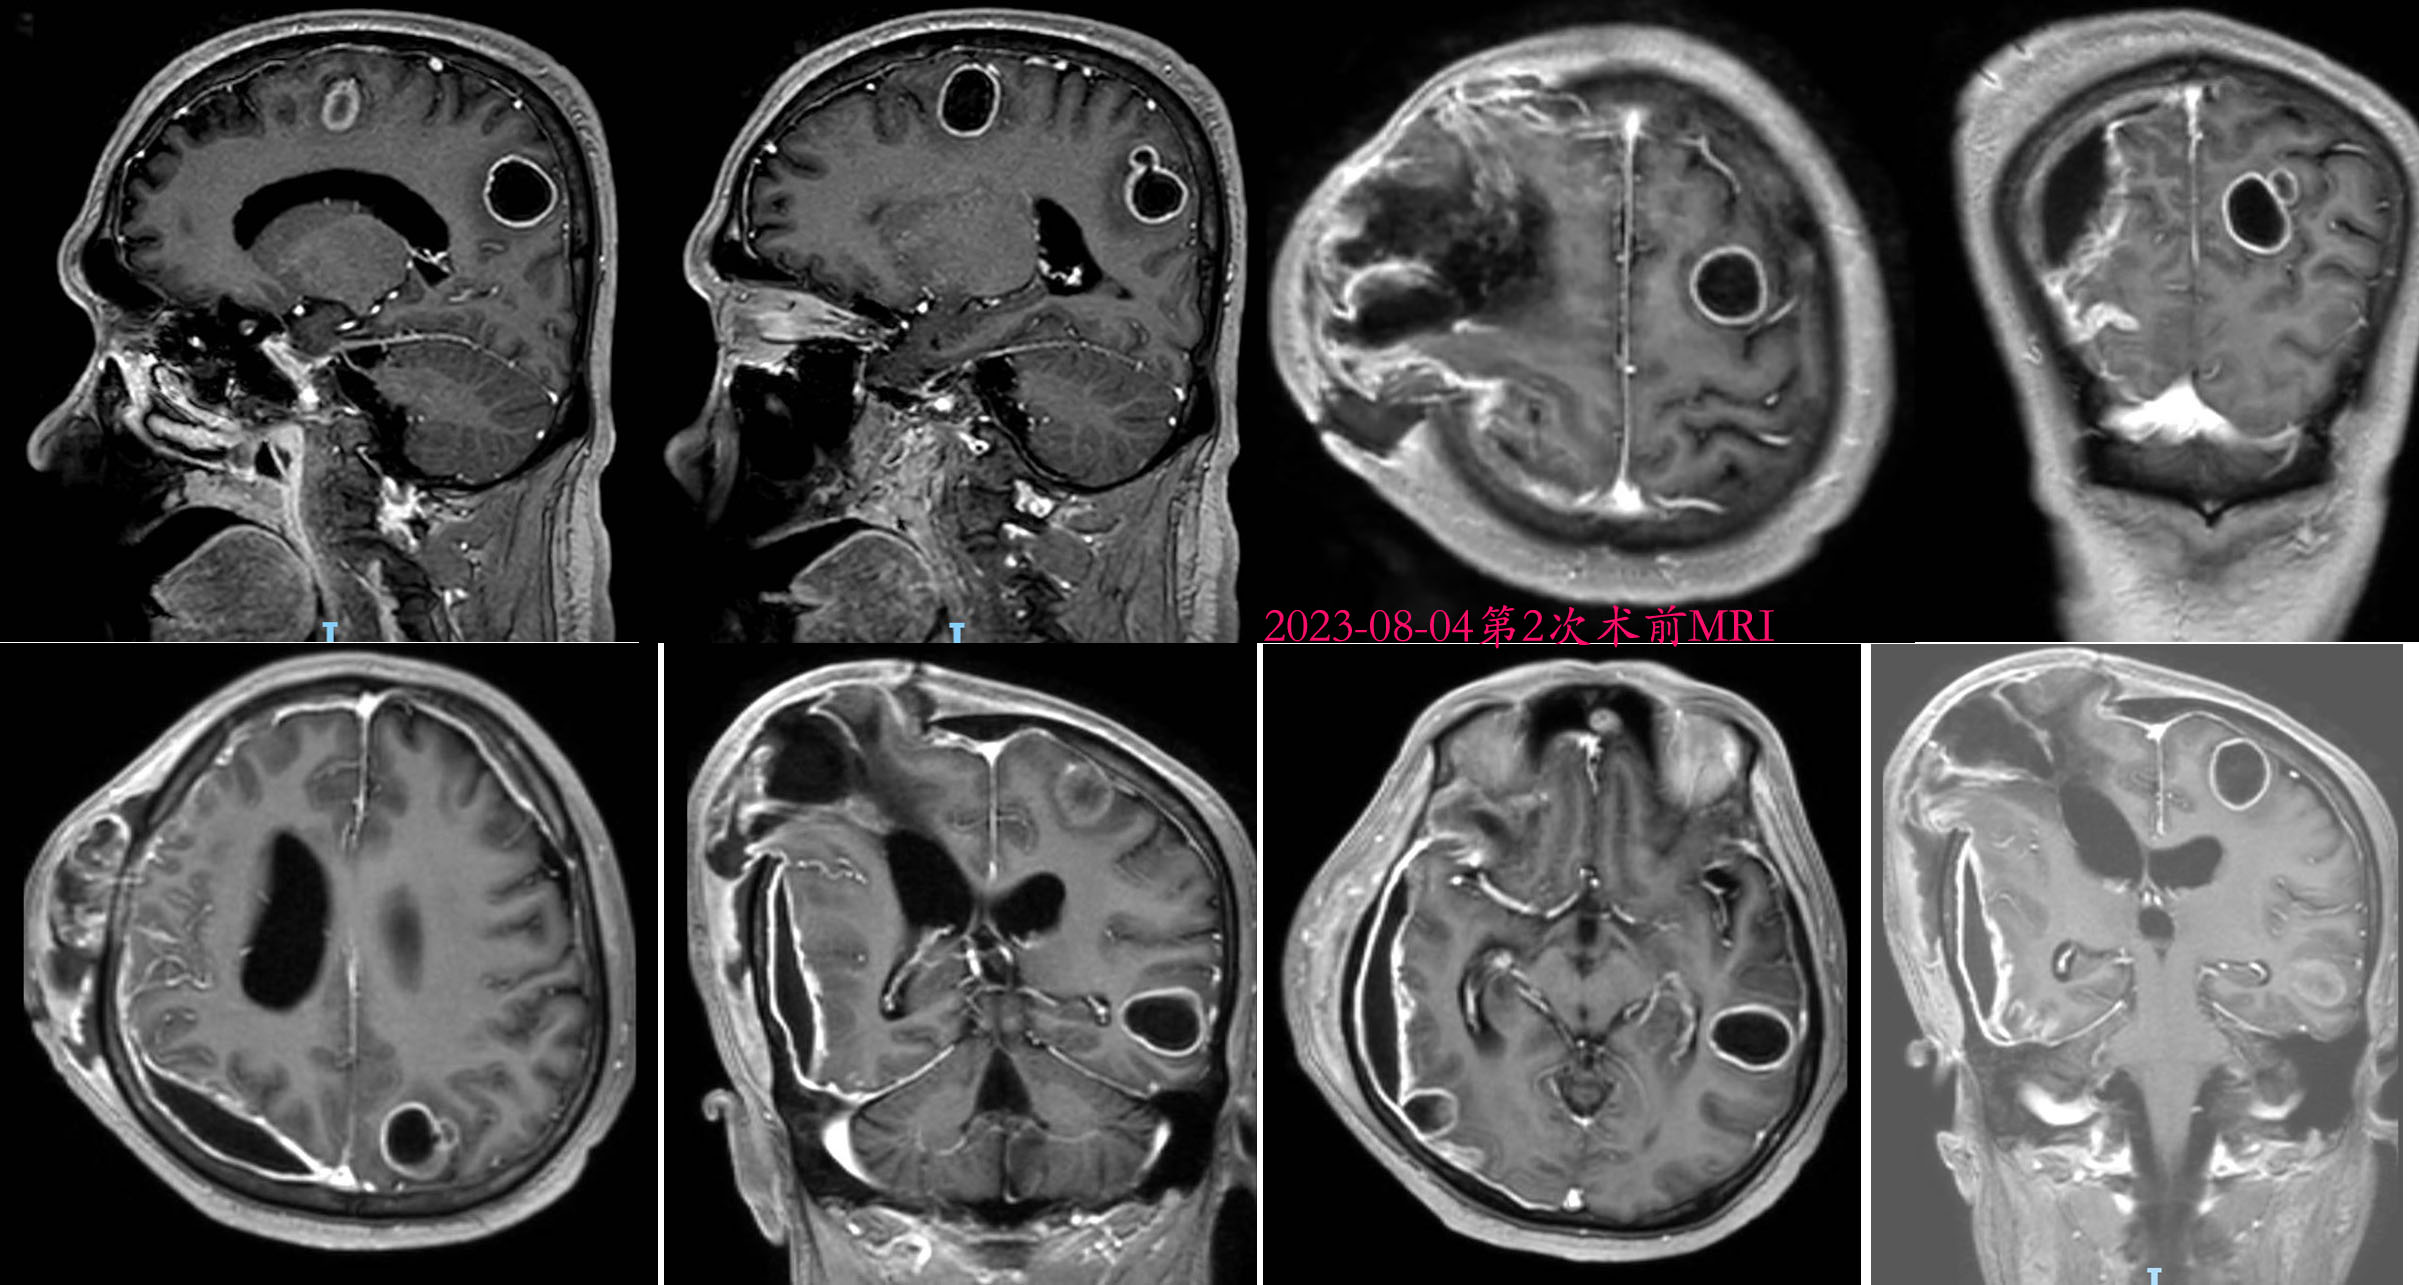

入院后完善相关术前准备及检查,头颅MRI提示:双侧大脑半球及胼胝体体部多发占位,考虑转移瘤可能,不除外脑脓肿。右侧额顶颞枕部硬膜下积液。注意脑疝形成。

2023-08-04头皮切口张力高,脑脊液漏,脓性分泌物流出。MRI可见左顶、左额、左枕、左颞、右额颞枕共5处脑脓肿,右侧额颞枕脓肿可一次手术切除,但其余4处需要分开开颅切除脓肿,先俯卧位,切除左顶、左额、左枕、左颞脓肿,后仰卧位,切除右侧额颞枕脓肿,术前取右侧大腿阔筋膜作为修补脑脊液漏。